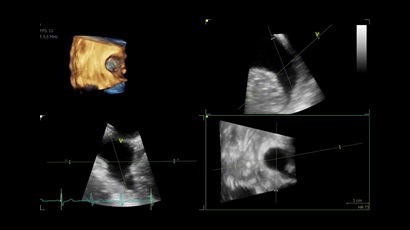

• Vivid IQ Premium с расширенным набором опций

• Vivid IQ 4D с поддержкой технологии объемной реконструкции

• Передовые технологии, такие как 4D чреспищеводная эхокардиография, ЭКГ, стресс-эхо, внутрисердечная ультразвуковая эхокардиография, тканевый доплер и другие.

4D:

Да

• 6VT (биплан/триплан).

• 4D AUTO AVQ - модуль автоматического выравнивания, сегментации и обсчета размеров кольца аортального клапана по объемным данным.

• 4D AUTO LVQ - модуль расчета массы миокарда ЛЖ на основе данных 4D-исследования.